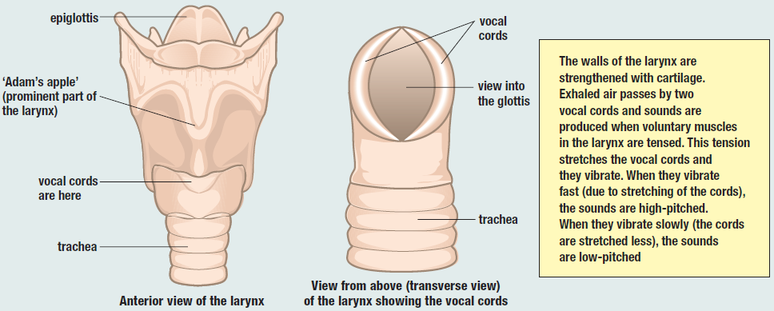

(3) Larynx:

The pharynx leads into the larynx which is also called the voice box. The larynx leads into the trachea, which is also called the wind pipe.

(3) Larynx:

The pharynx leads into the larynx which is also called the voice box. The larynx leads into the trachea, which is also called the wind pipe.